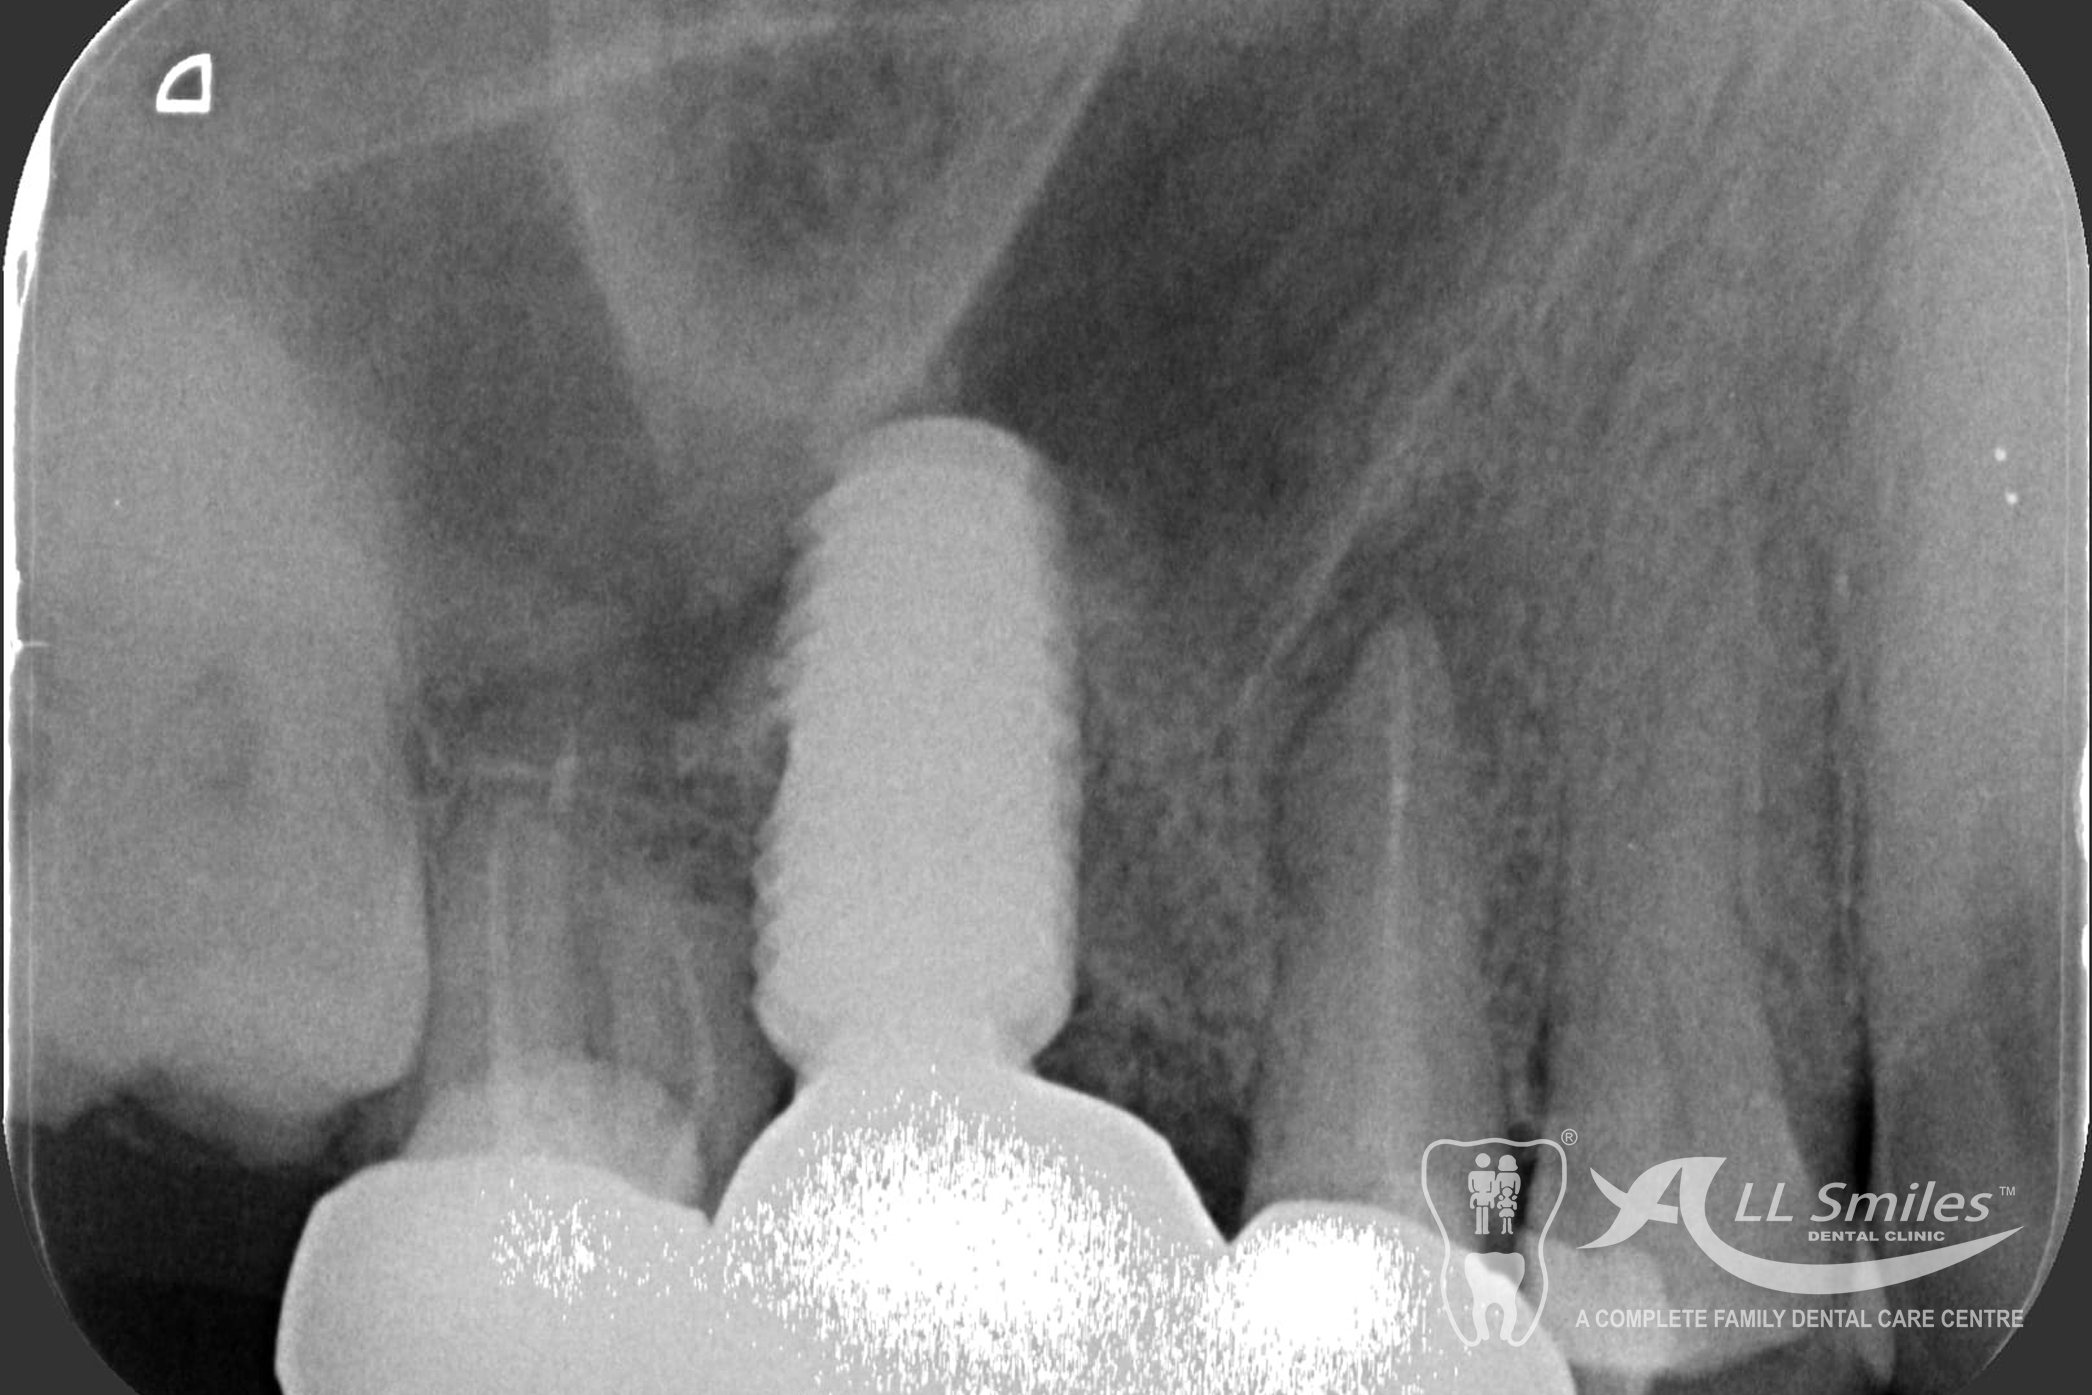

The dental implant procedure is divided into stages. The first stage involves the placement of the implant into the jawbone, which usually takes 1-2 hours. After this, there is a healing period of 6-8 weeks during which the implant fuses with the surrounding bone tissue. Once the implant has healed, a small connector called an abutment is attached to the implant, followed by the attachment of a dental crown, bridge, or denture.

Successful tooth implant procedures require a foundation of healthy bone and gums. Before starting an implant procedure, we’ll assess your health and work with you to create a plan to resolve gum disease or other issues. Expect your first visit to take about 90 minutes and include an exam, x-rays, thorough cleaning, and plenty of time to speak with your dentist.